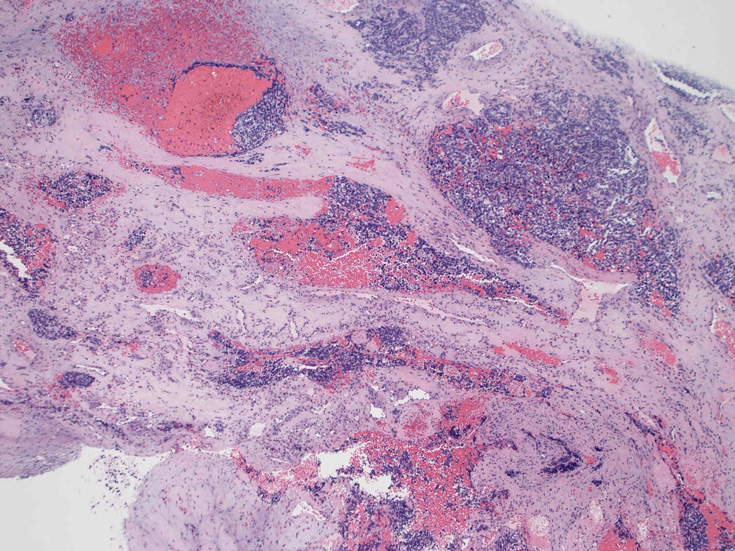

30歳代男性 鼻腔腫瘤の生検組織

厳密にはalveolar patternが明らかではなく, solid typeに入る症例かもしれない。異型細胞増殖胞巣が線維化組織に取り囲まれるように散在している. 小さな生検組織のため全体像が不明である。